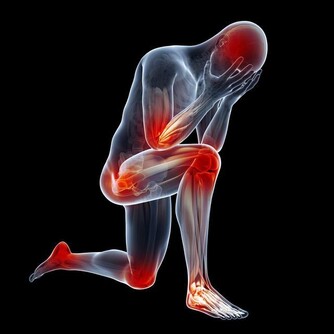

維生素B12缺乏症是世界上最常見的營養缺乏症之一,特別是在老年人中。維生素B12在保持身體的神經和血細胞健康是非常重要的。因此,當這種維生素水平不足時,身體就會受到影響。

由於其在不同身體過程中的多種用途,當缺乏這種維生素時,人們肯定會遭受痛苦。對於孕婦來說,維生素B12水平低可能意味著神經管缺陷的風險增加。對於其他人,他們可能有患2型糖尿病和其他健康問題的風險。